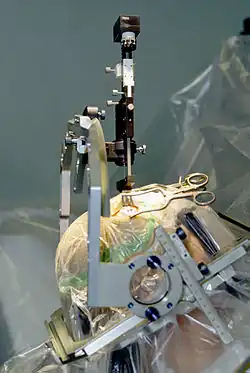

Basically it involves the implantation of electrodes into the brain. Usually they are positioned in the subthalamic nucleus but sometimes other targets can be used including the internal segment of the globus pallidus and the thalamus. Small electrical pulses are applied through these electrodes by means of a controller implanted under the skin of the chest or abdomen.

DBS is an expensive procedure and not without risks and is therefore only usually prescribed when other forms of Parkinson's treatment have lost their effectiveness or are accompanied by severe side effects. Patients are carefully assessed for whether they are likely to benefit from it. Lack of response to levodopa is one counter indication because DBS and dopamine replacement therapy basically target the same cause of motor symptoms, the disruption of the circuitry of the basal ganglia.

- It involves invasive brain surgery which entails risk.